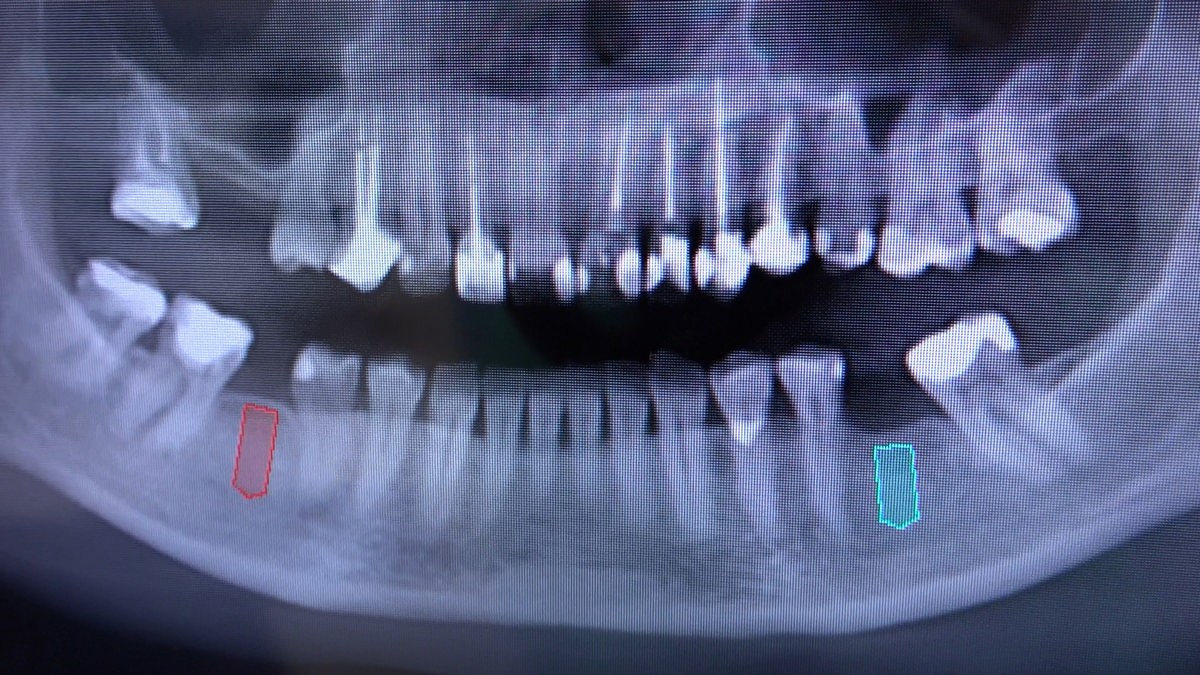

PRACTICULUM IMPLANTOLOGII - SEZON X - SESJA 4 - GRUPA B